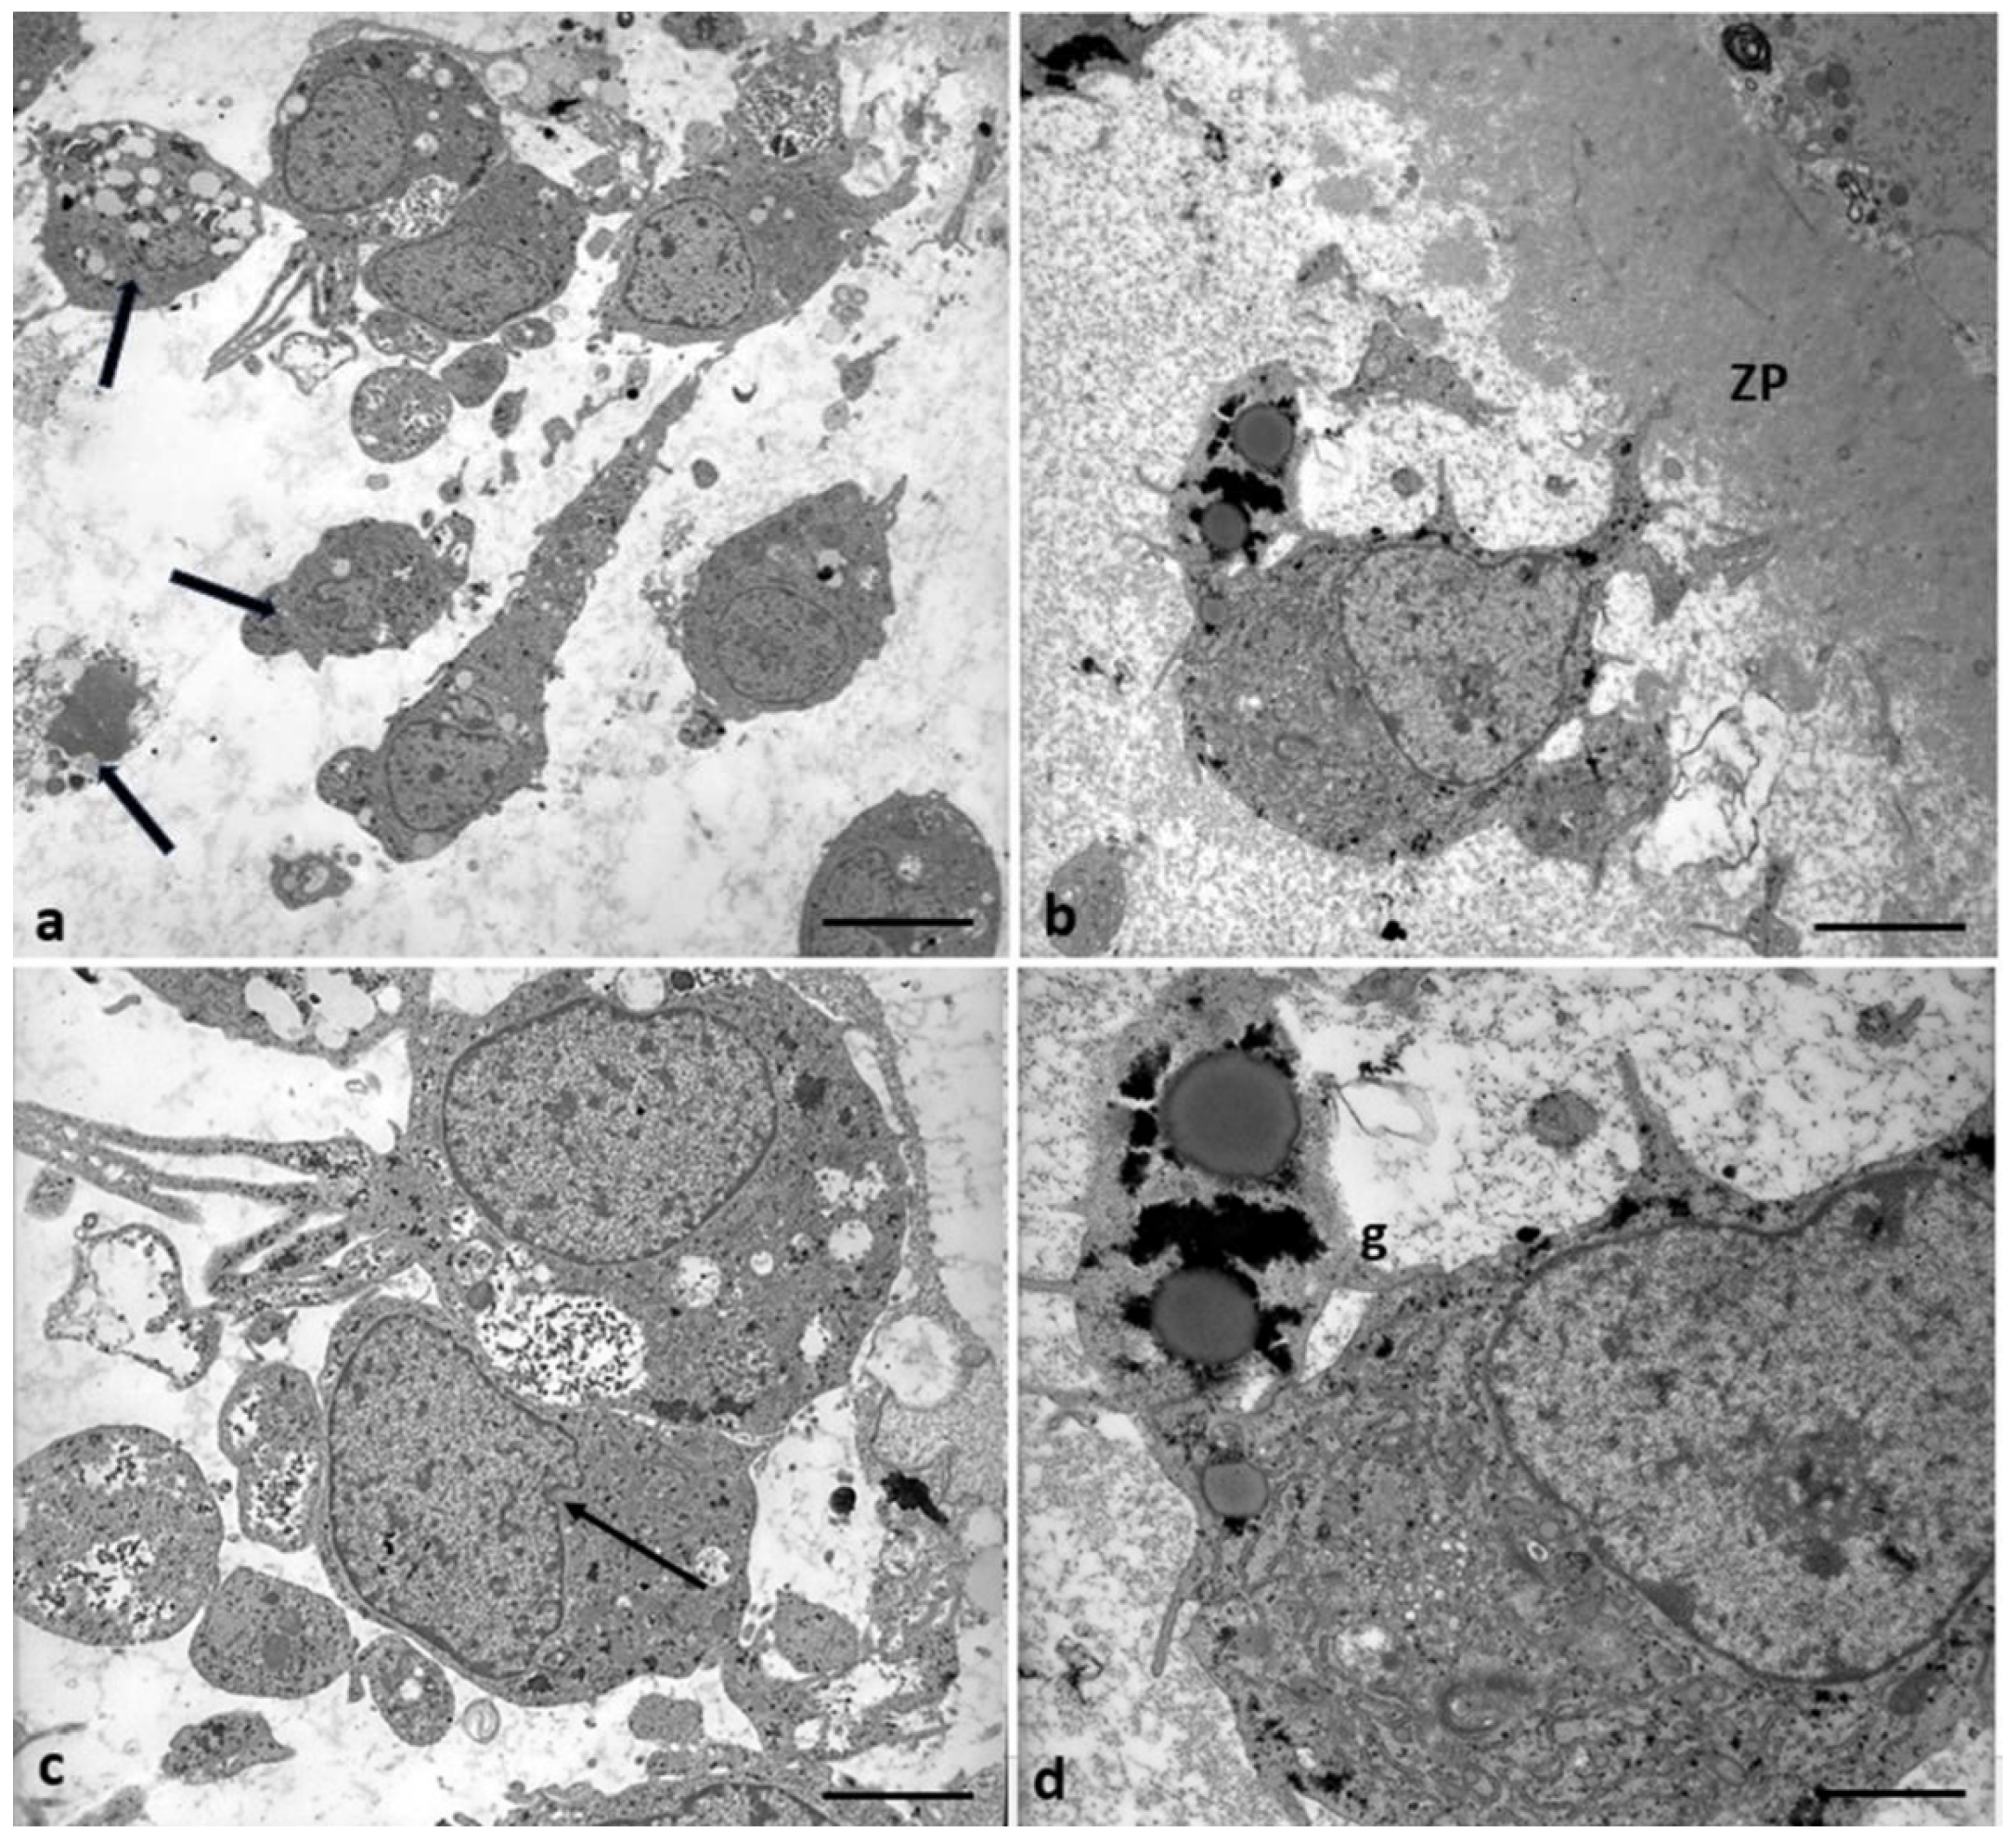

3.2. Electron microscopy

4.2. Cumulus cells ultrastructural changes heavy metals-dependent.

5. Conclusions